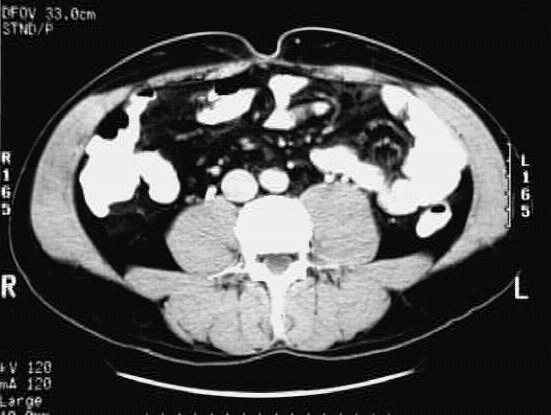

Abdomen- Abdomen Cross 8 :